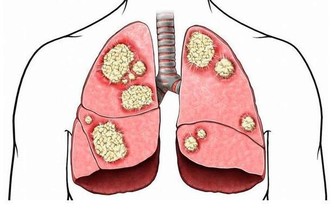

夏天毒素如果無法排出體外,就會向內滲透,血液毒素垃圾過多就會形成血栓,所以在夏季得心腦血管疾病的人也會很多,因此在夏季最熱的三伏天我們也要注意排血毒。